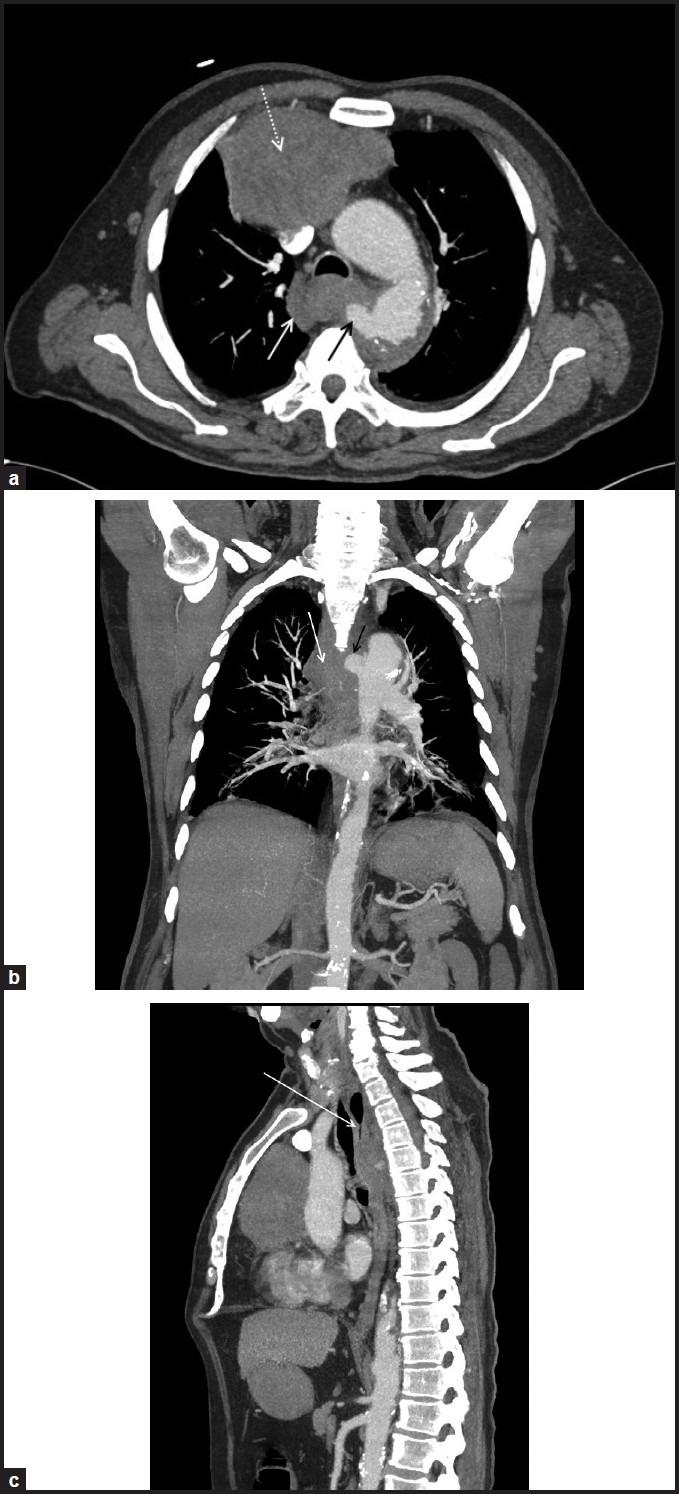

Aorto-esophageal fistula secondary to penetrating atherosclerotic ulcer.

Aorto-esophageal fistula (AEF) is a rare and life threatening condition, which can be rapidly fatal. More than half of such cases are secondary to aortic aneurysm rupture. There are only two previous reports describing AEF caused by penetrating atherosclerotic ulcer. We present multidetector computed tomography findings in a case of AEF secondary to penetrating atherosclerotic ulcer.

主动脉食管瘘(AEF)是一种罕见且危及生命的疾病,可迅速致命。超过半数的此类病例继发于主动脉瘤破裂。此前仅有两份报告描述了由穿透性动脉粥样硬化溃疡引起的AEF。我们报告了一例继发于穿透性动脉粥样硬化溃疡的AEF的多排螺旋计算机断层扫描结果。